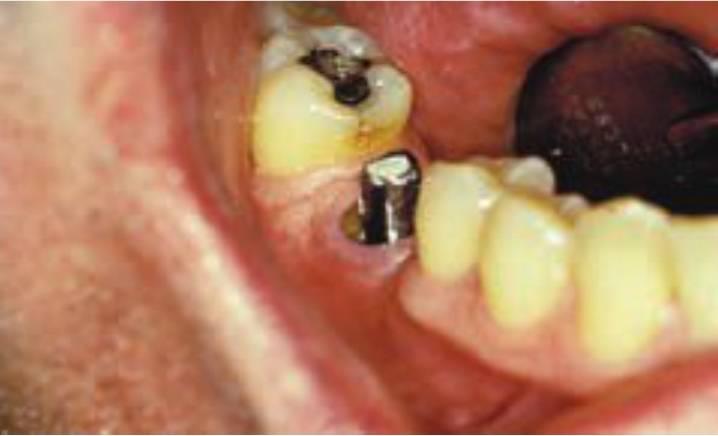

Un tratamiento opcional para sustituir a un solo diente perdido es un implante dental unitario (fig. 1-8). Durante años, los pacientes debían aparcar sus deseos y aceptar las limitaciones de una PPF. Sin embargo, muchos sienten que el método más natural de reemplazar un diente es emplean do un implante, más que preparando los dientes adyacentes y uniéndolos con una prótesis. Los motivos principales para sugerir el uso de las PPF fueron su facilidad clínica y su reducido tiempo de tratamiento. En cualquier caso, si se expandiera este concepto, las extracciones reemplazarían a las endodoncias y las dentaduras podrían incluso reemplazar a las ortodoncias. El motivo principal para sugerir o llevar a cabo un tratamiento no debería tener relación con el tiempo de tratamiento o la dificultad del procedimiento, sino que debería ser la mejor solución posible a largo plazo para cada individuo.

Salvo algunas limitaciones y desafíos clínicos evidentes, el implante dental unitario representa un tratamiento de elección desde el doble punto de vista de la salud y el valor. Cuando los dientes adyacentes están sanos, o el paciente rechaza su preparación para la fabricación de una unidad tradicional de restauración de tres unidades, un implante dental posterior unitario es una solución excelente (fig. 1-9). Las ventajas relacionadas con la salud de esta modalidad respecto a la restauración fija parcial se enumeran en el cuadro 1-2 e incluyen disminución del riesgo de caries y de enfermedad periodontal, disminución del riesgo de pérdida de un pilar dental por caries o fracaso del tratamiento endodóncico y mejoría estética (fig. 1-10).